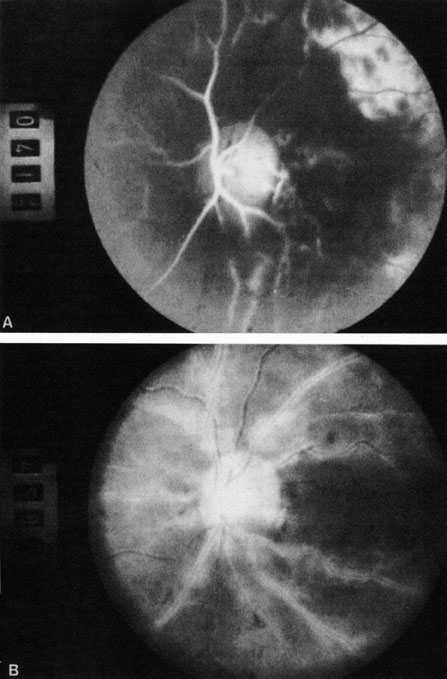

CAROTID ARTERY DISEASE The principal cause of chronic arterial obstruction is usually some kind of carotid artery disease. Atherosclerosis is the most common cause of carotid artery disease in the United States but there are other causes, such as moyamoya disease,148 fibromuscular dysplasia,149 and irradiation.150 Atherosclerosis is a disease affecting medium-sized arteries in humans. The primary symptoms of carotid artery disease are caused by the atheromatous or fibromuscular plaque.151,152 Atherosclerosis may result in narrowing (obstruction) or occlusion of the artery or in embolization. The bifurcation of the common carotid artery into the external and internal carotid artery is one of the sites at particular risk for atheromatous disease.153 The eye is frequently involved in atheromatous disease of the carotid artery bifurcation because the ophthalmic artery is one of the first branches of the internal carotid artery in the neck. Carotid artery disease can be manifest by a variety of ocular and non ocular symptoms. The ocular manifestations are important—not only because they occur in many patients with carotid insufficiency154 but also because they often are the first indication that carotid artery disease exists. There are many ways that patients with carotid artery disease present to the ophthalmologist.8 Some present with a TIA. If the TIA involves the carotid system, the symptoms include hemiparesis, hemisensory loss, aphasia, and transient monocular blindness (amaurosis fugax).155 Another group of patients have symptoms that are purely ocular. These patients present with one of several symptoms, such as (i) partial or complete visual loss due to an artery obstruction, (ii) decreased visual acuity, or (iii) pain resulting from the ocular ischemic syndrome. Other patients are asymptomatic and any ocular findings consistent with carotid artery disease are incidental. Amaurosis Fugax The type of TIA known as amaurosis fugax is the most common symptom of carotid artery disease.154,156 Amaurosis fugax is characterized by a sudden, painless, monocular loss of vision that typically lasts between 2 and 10 minutes. The patient frequently describes his or her vision as being “dark” or “dim.” The return of vision can be sectorial or altitudinal and is occasionally described as a “curtain rising.” Generally, the vision returns to normal immediately after an attack. The frequency of these attacks varies from 1 or 2 attacks per month to 10 or 20 per day. The retina—if observed during an amaurotic attack—may be normal155 or it may show obstruction (such as in central retinal artery obstruction). It may exhibit migratory white retinal emboli (within the retinal arterioles and in association with disruption of the arterial circulation)157 or it may show cholesterol emboli moving through the arterial system.155 It is important to recognize amaurosis fugax as a TIA because it is frequently caused by microembolization from an atheromatous ulcerative lesion in the ipsilateral extracranial carotid artery, at least in older patients.158,159 Approximately one-third of all patients with an untreated TIA can be expected to have a stroke; this rate is about four times greater than that of an age-matched population.160 It must be noted, however, that not all amaurosis fugax and other forms of TIA are caused by carotid artery disease. Other causes of amaurosis fugax include temporal arteritis,161 pseudotumor cerebri,161 migraine,161 structural cardiac defects,162 ophthalmic artery stenosis,163 ophthalmic artery aneurysms, hematology disorders,164,165 ocular hypertension,160 arterial hypotension, and vasospasm.165 A group—usually younger patients—may have no identifiable disease.161,162,167 Ocular Ischemia There are several forms of chronic arterial obstructions that occur in carotid artery disease. These typically result from hypoperfusion of the retina caused by either stenosis or the complete obstruction of either the extracranial internal or the common carotid artery. One form of chronic arterial occlusion is a unilateral retinopathy that is ipsilateral to the carotid artery lesion and is characterized by cotton-wool patches, dilated arterioles and veins, an absence of hemorrhages, and normal vision. This retinopathy was first recognized as a sign of carotid artery disease by Hollenhorst154 in 1958, although such changes had been previously noted after ligation of the common and external carotid arteries in the treatment of traumatic carotid cavernous fistula.168 In a milder form of this retinopathy, the only abnormality may be larger retinal arterioles on the side of a ligated carotid artery in patients with hypertension169 or asymmetric hypertensive retinal vascular changes, in which the eye ipsilateral to the carotid lesion has the fewer changes.8 Another type of chronic ophthalmic artery obstruction produced by hypoperfusion caused by stenosis or occlusion of the ipsilateral extracranial carotid artery was first reported by Hedges170 and termed venous stasis retinopathy by Kearns and Hollenhorst.171 Venous stasis retinopathy is probably not a good term for this condition, however, because the basic mechanism involves reduction of the arterial inflow, not the venous outflow. Even more confusion has resulted from the use of the term to describe the features of the nonischemic form of central retinal vein obstruction.172 A better term is hypoperfusion or hypotensive retinopathy.172 Klijin and co-workers414 found this type of chronic ocular ischemia in approximately one-third of patients studied with symptomatic carotid artery occlusive disease. Hypoperfusion retinopathy is characterized by dot and blot hemorrhages in the midperiphery of the fundus, by venous tortuosity and engorgement, by microaneurysms, and by the occasional sludging of blood within the veins. Fluorescein angiography may show areas of capillary nonperfusion; it may also show microaneurysms in the midperiphery and slow arm to retina or arteriovenous transit time (Fig. 9A and 9B).174 The condition does not usually affect the posterior pole, and patients typically have normal visual acuity, although an occasional patient may have macular edema.174 The entire periphery of the eye is usually affected, although there may be more hemorrhages in one quadrant than another. Patients occasionally experience ocular discomfort or eye pain despite normal intraocular pressure. Reduction of the ophthalmic arterial pressure is a pathognomonic feature. Disc edema and disc collaterals are generally not present. The electroretinogram shows abnormalities in both the a- and b-waves (see Fig. 9C).